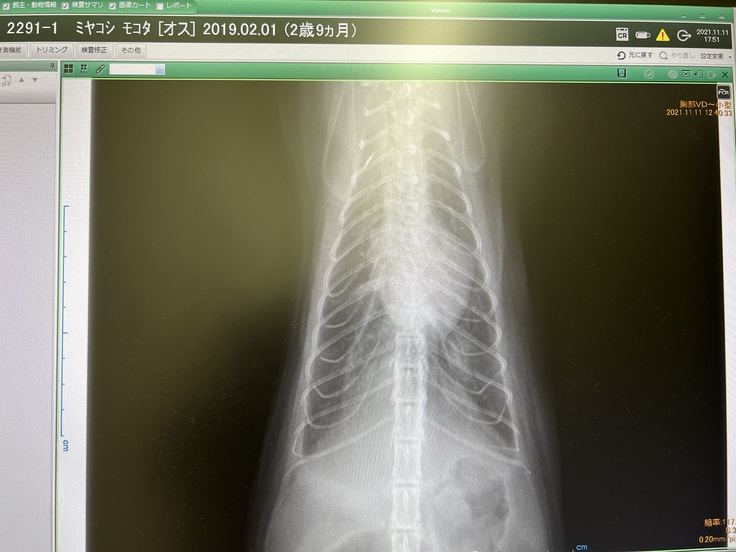

夜間救急についてから、すぐにレントゲンを撮ると、重度の肺水腫と診断されました。レントゲンを見ると肺が真っ白でした。

レントゲンでは真っ白だった肺は半分くらい綺麗になっていました。利尿剤がきいておしっこをたくさ?出してくれたおかげです。

心臓は胸郭との比率でみて74%ほど肥大していると言われました。本来は60%が理想です。

↑白いモヤがなくなり綺麗になった肺のレントゲンです。